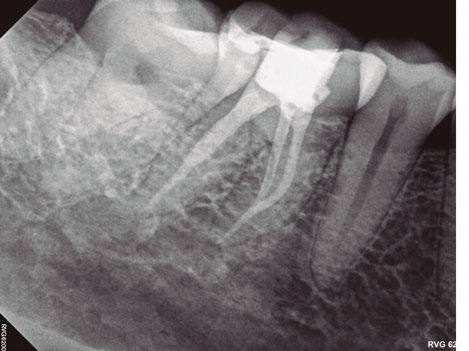

A 48-year-old female patient presented to the graduate endodontic clinic with a referral to evaluate and treat tooth No. 11 through the existing crown. The patient’s chief complaint was, “I was told a year ago I had an infection, but it hasn’t bothered me. They told me I needed a root canal to get rid of the infection.” The patient had no significant health history or any known drug allergies. Dental history for tooth No.11 included multiple restorations followed by a final core and crown in 2019. The adjacent tooth, No. 12, was replaced with an implant in 2018 and restored in 2019, 6 months following final crown of tooth No. 11. Upon examination of records, a periapical radiolucency on tooth No. 11 was visible on the day of crown fabrication and delivery (Figure 1). There was no note of this lesion in the patient’s record. An updated radiograph was taken during a periodic oral exam in September of 2023 showing clear delineation of the periapical radiolucency on tooth No.11 (Figure 2).

Figure 1 (left): Periapical radiograph taken at the time of tooth No. 11 crown delivery in 2018 with a periapical radiolucency extending distally toward implant No. 12. Figure 2 (right): Updated periapical radiograph taken in 2023 during a periodic oral exam showing clear delineation of a periapical radiolucency associated with tooth No. 11

Figure 3: Periapical radiographs taken during endodontic consultation in 2023. Periapical radiolucency originated from tooth No. 11 and extended toward implant No. 12. Calcification was appreciated in the coronal portion of the canal space on tooth No. 11